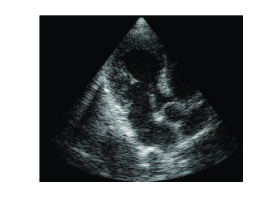

To demonstrate the equivalence of beamforming in time and frequency, we applied both methods on in vivo cardiac data yielding the images shown in Fig. 3. The imaging setup is that described in Section II-B with MHz. As can be readily seen, the images look identical.

Comparison of the resulting images was performed by calculating the structural similarity (SSIM) index [16], commonly used for measuring similarity between two images. The first line of Table I summarizes the resulting values. These values verify that both 1D signals and the resulting image are extremely similar.

(a)

(b)